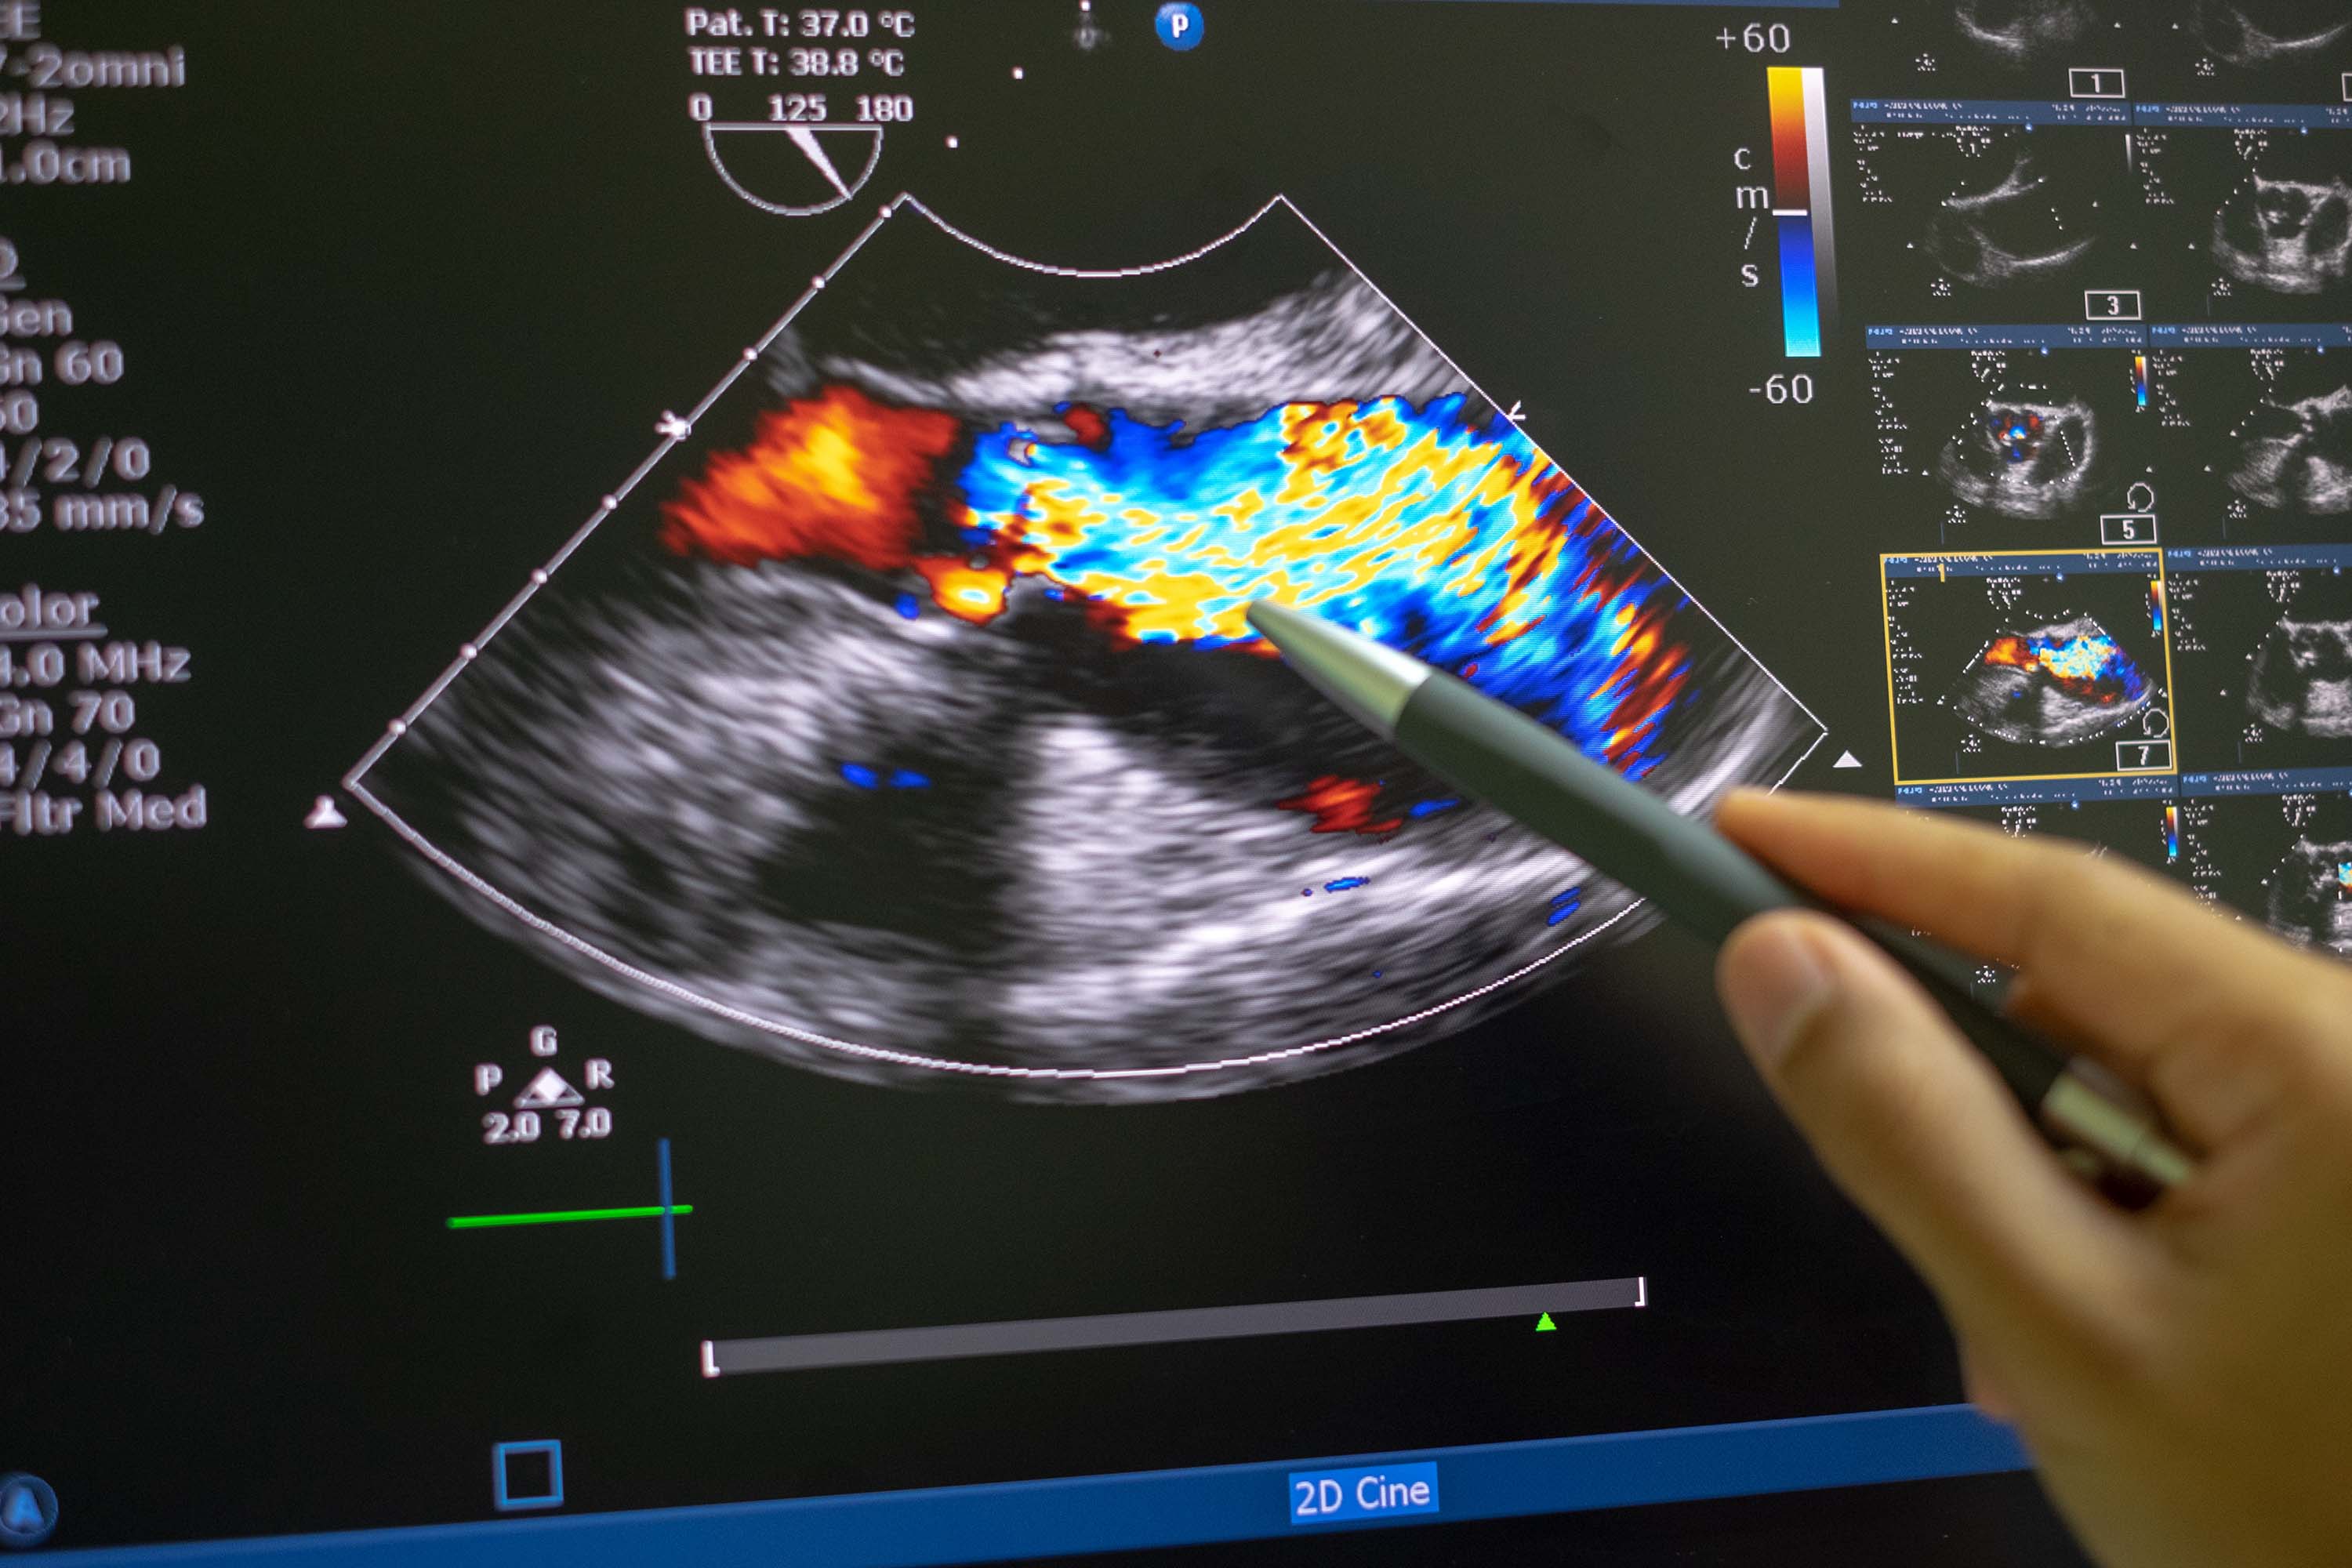

The unskilled user is asked to perform a few 2D Bmode scans of the heart without the need for accurate positioning of the ultrasound transducer. Next, our echo system quickly reconstructs the 3D shape of the heart accurately, and then performs rapid and automatic quantification of various measurements, such as ejection fraction, chamber volume, wall thicknesses, chamber dimensions and myocardial strains, etc. The invention combines years of expertise from clinical cardiology, Computational Bioengineering, and AI. We are seeking industry collaboration opportunities to accelerate commercial development and shorten time to market.